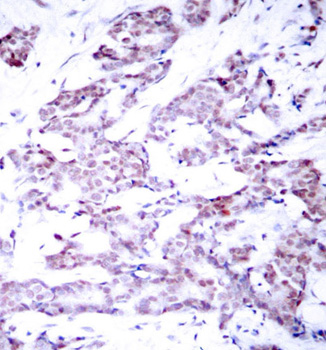

Immunohistochemical analysis of paraffin-embedded human breast carcinoma tissue, using Phospho-STAT6-T645 antibody.

Tested applicationsIHC

Recommended DilutionIHC 1:50 - 1:100

ImmunogenA phospho specific peptide corresponding to residues surrounding T645 of human STAT6